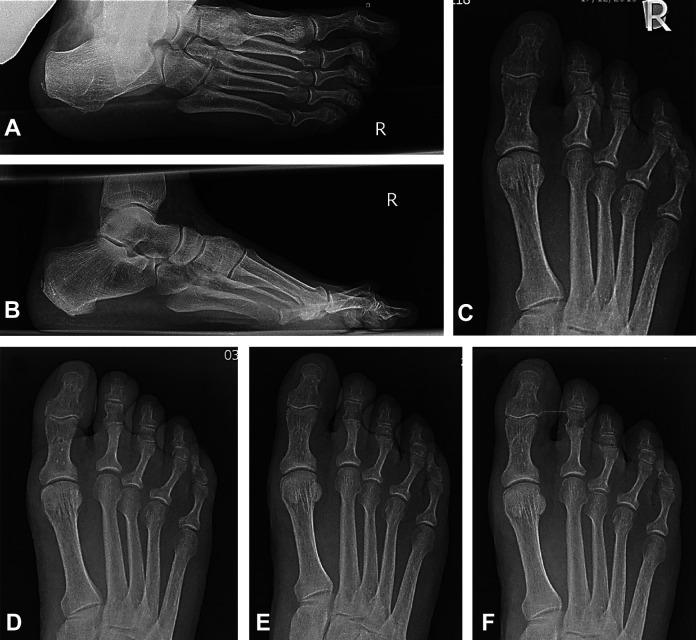

A novel biointegrative implant was developed for proximal interphalangeal joint (PIPJ) arthrodesis to treat hammertoe deformity. Composed of continuous reinforcing mineral fibers bound by bioabsorbable polymer matrix, the implant demonstrated quiescent, gradual degradation with complete elimination at 104 weeks in animal models. This prospective trial assessed the implant's safety, clinical performance, and fusion rate of PIPJ arthrodesis for hammertoe correction.

Twenty-five patients (mean age 63.9±7.5 years) who required PIPJ arthrodesis were enrolled at 3 centers. Outcomes included radiographic joint fusion, adverse events, pain visual analog scale (VAS) score, Foot and Ankle Ability Measure (FAAM) Activities of Daily Living (ADL) score, and patient satisfaction. Patients were evaluated 2, 4, 6, 12, and 26 weeks postoperatively.

Twenty-two patients (88%) achieved radiographic fusion at 26 weeks. All joints (100%) were considered clinically stable, with no complications or serious adverse events. Pain VAS improved from 5.3±2.5 preoperatively to 0.5±1.4 at 26 weeks postoperatively. FAAM-ADL total scores and level of functioning improved by mean 19.5±19.0 points and 24.4±15.7 percentage points, respectively, from preoperation to 26 weeks postoperation. Improvements in pain VAS and FAAM scores surpassed established minimal clinically important differences. All patients were very satisfied (84%) or satisfied (16%) with the surgery. Patient-reported postoperative results greatly exceeded (72%), exceeded (20%), or matched (8%) expectations.

This prospective, multicenter, first-in-human clinical trial of a novel biointegrative fiber-reinforced implant in PIPJ arthrodesis of hammertoe deformity demonstrated a favorable rate of radiographic fusion at 12 and 26 weeks, with no complications and good patient-reported clinical outcomes.